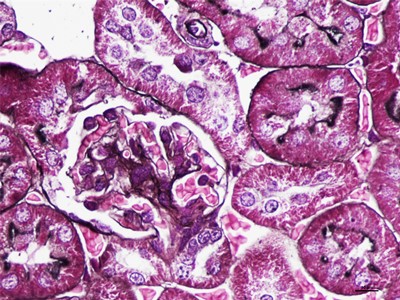

HE染色简称苏木精是是一种由碱性染液苏木精和酸性染液伊红构成的一种染色方法。是通显微镜下观察病理切片里病变的组织学形态变化来诊断疾病的,适用于胚胎学、病理学,生物医学,病理学教学与科研。HE染色对碱性染料和酸性染料亲和力都比较弱的现象称为中性。组织切片苏木素染色、分化与反蓝:将水化后的组织样本的切片使用PBS溶液浸泡清洗,每次浸泡5min,总共清洗3次。之后用移液枪吸取已经预先配置好的苏木素染色液,每个组织切片滴加100ul,充分染色10min。切片经HE染色后,要彻底脱水透明,才能用新疆中性树胶封盖。he染色对于贴壁生长细胞,胰酶消化,调整细胞浓度约1×105/ml,滴加于盖玻片上(置于6孔板中),培养相应时间后,取出细胞爬片,用PBS 洗涤3次。着色情况与组织或细胞的种类有关。切片在苏木素染液中停留过长;或切片太厚;或分化时间太短。这种情况首先镜下看看切片厚度(最佳厚度1-2层细胞核),要么重新染色,要么重新制片。染色的最终结果是:细胞核呈蓝色、胞质、肌纤维、胶原纤维和红细胞呈深浅不一样的红色,病理技术服务提醒:在进行HE染色需要染色时间,脱水,染色时间不一样,需要等 ,明确HE评判标准。